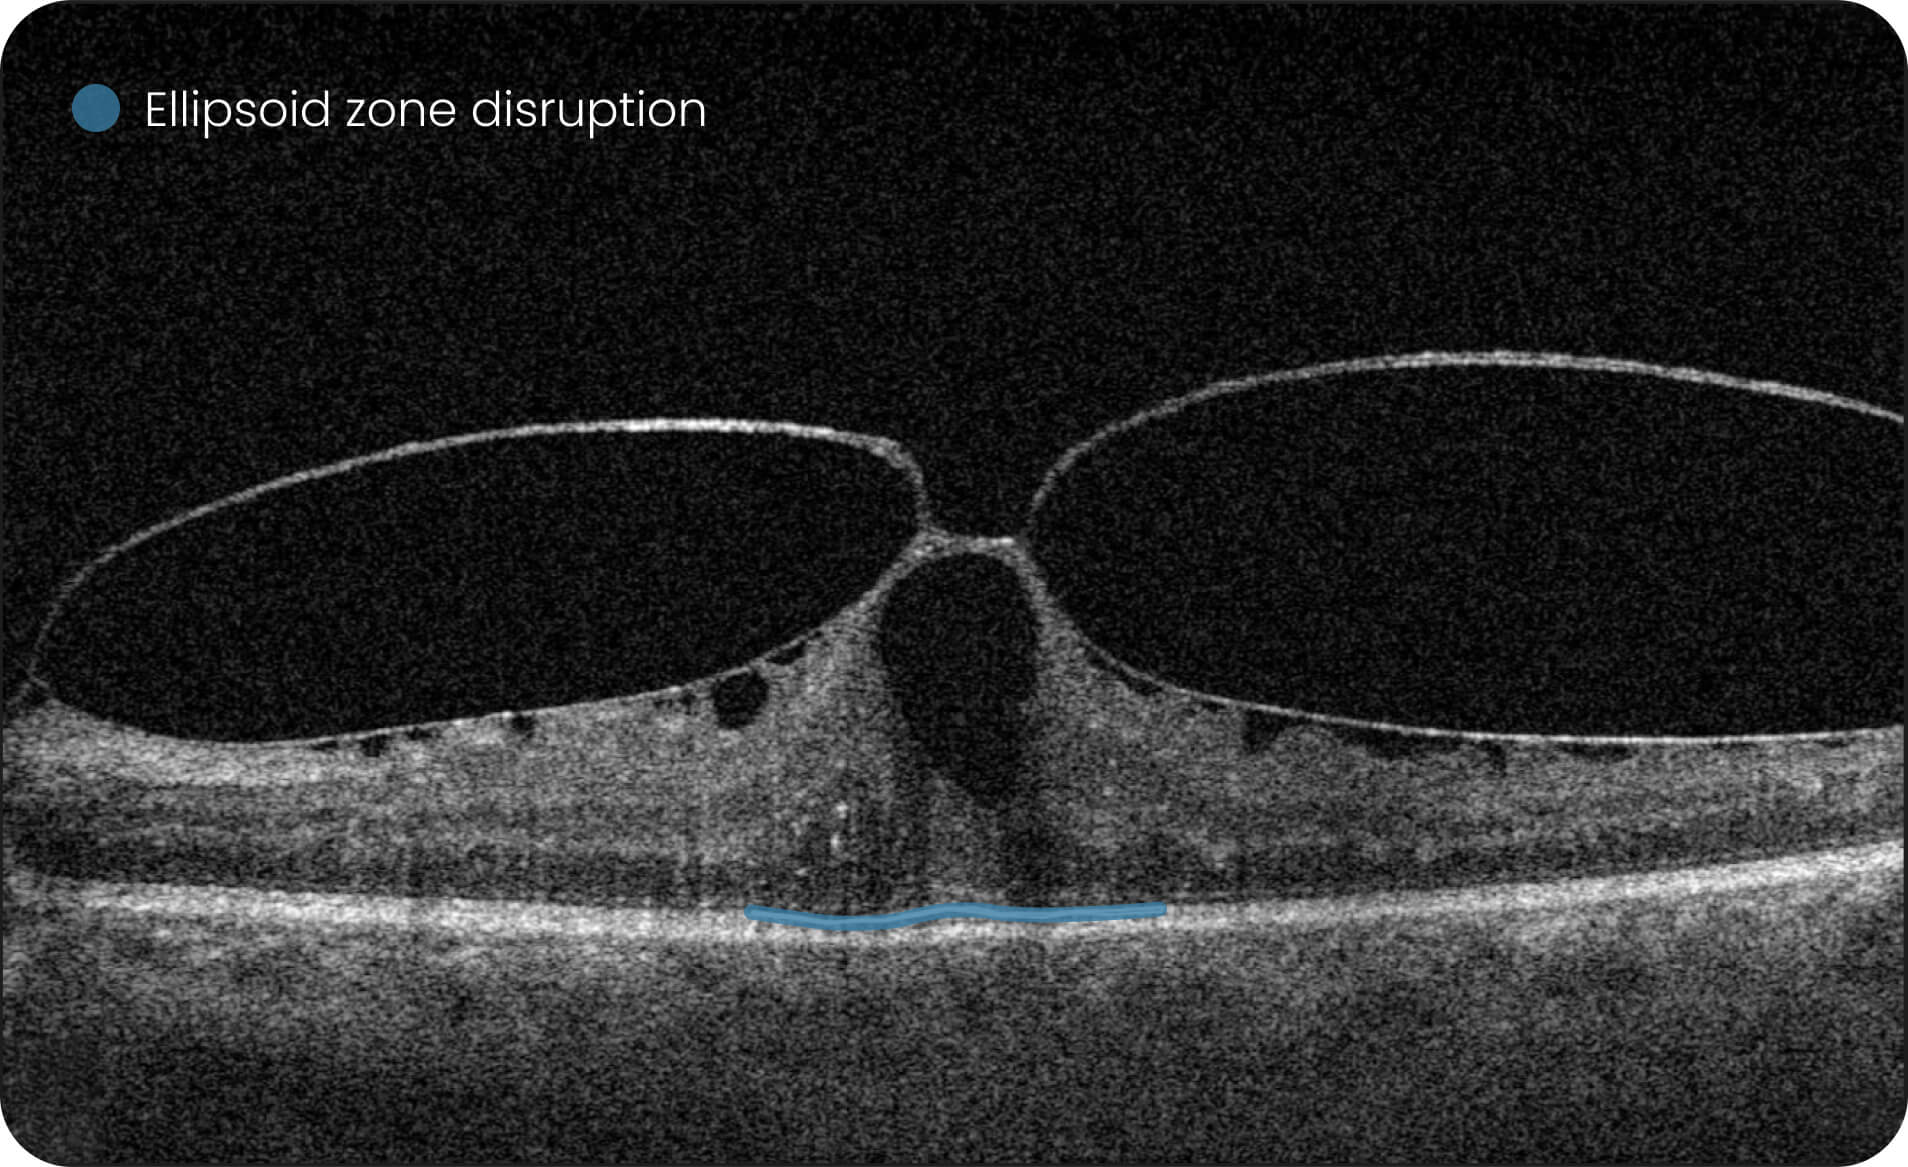

Characterization and visualization of OCT features commonly studied in Geographic Atrophy (GA), including hypertransmission, RPE atrophy, neurosensory retinal atrophy, and EZ changes.

Quantitative, image-derived measurements of GA-related features and associated biomarkers for research analyses.

- 40+retinal biomarkers studied in research across 30+ retinal conditions. For Research Use Only. Not for diagnostic procedures.

- Quantitative exploration of 40+ biomarkers for Research Use Only. Not for diagnostic procedures.